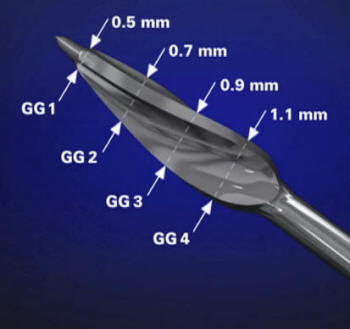

Fresas de

Gates Glidden

El

ensanchador Gates Glidden tiene un extremo

cortante corto, en forma de llama, con hojas

cortantes laterales levemente espiraladas

con ángulo muy inclinado respecto de la

vertical. Generalmente tiene una pequeña

guía no cortante en su extremo para

minimizar su potencial de perforación de la

superficie radicular. Ver imagen

izquierda

La cabeza

cortante está conectada al vástago por un

fino y largo cuello. Está numerado del 1 al

6 mediante marcas en el tallo del

instrumento. Se utilizan para la ampliación

y conformación de los conductos después del

limado seriado y ensanchamiento con limas,

en sus tercios cervical y a veces hasta el

tercio medio. Ver imagen derecha

Los taladros

Gates Glidden están diseñados con un punto

débil en la parte del eje más cercana a la

pieza de mano, de forma tal que el

instrumento fracturado pueda ser retirado

fácilmente del conducto. Se fabrican de acero

inoxidable y con un largo desde la punta hasta el

contrángulo de 18 mm.